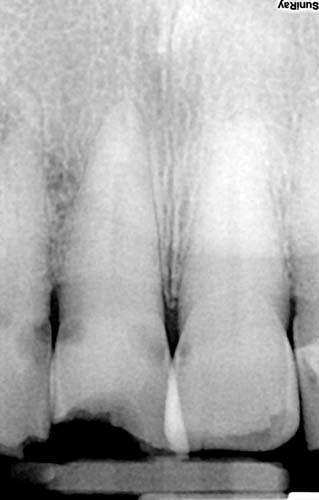

At 94, the patient still had a full set of natural teeth, thanks to a lifelong commitment to oral care, but she now suffered from compromised hygiene, xerostomia and a tendency to retain some food in her mouth. A radiograph revealed extensive caries, but the bone was excellent. Fortunately, she is cared for by a loving daughter who wanted her mother’s tooth restored for her comfort and appearance.

Fig. 2: Radiograph of incisor.